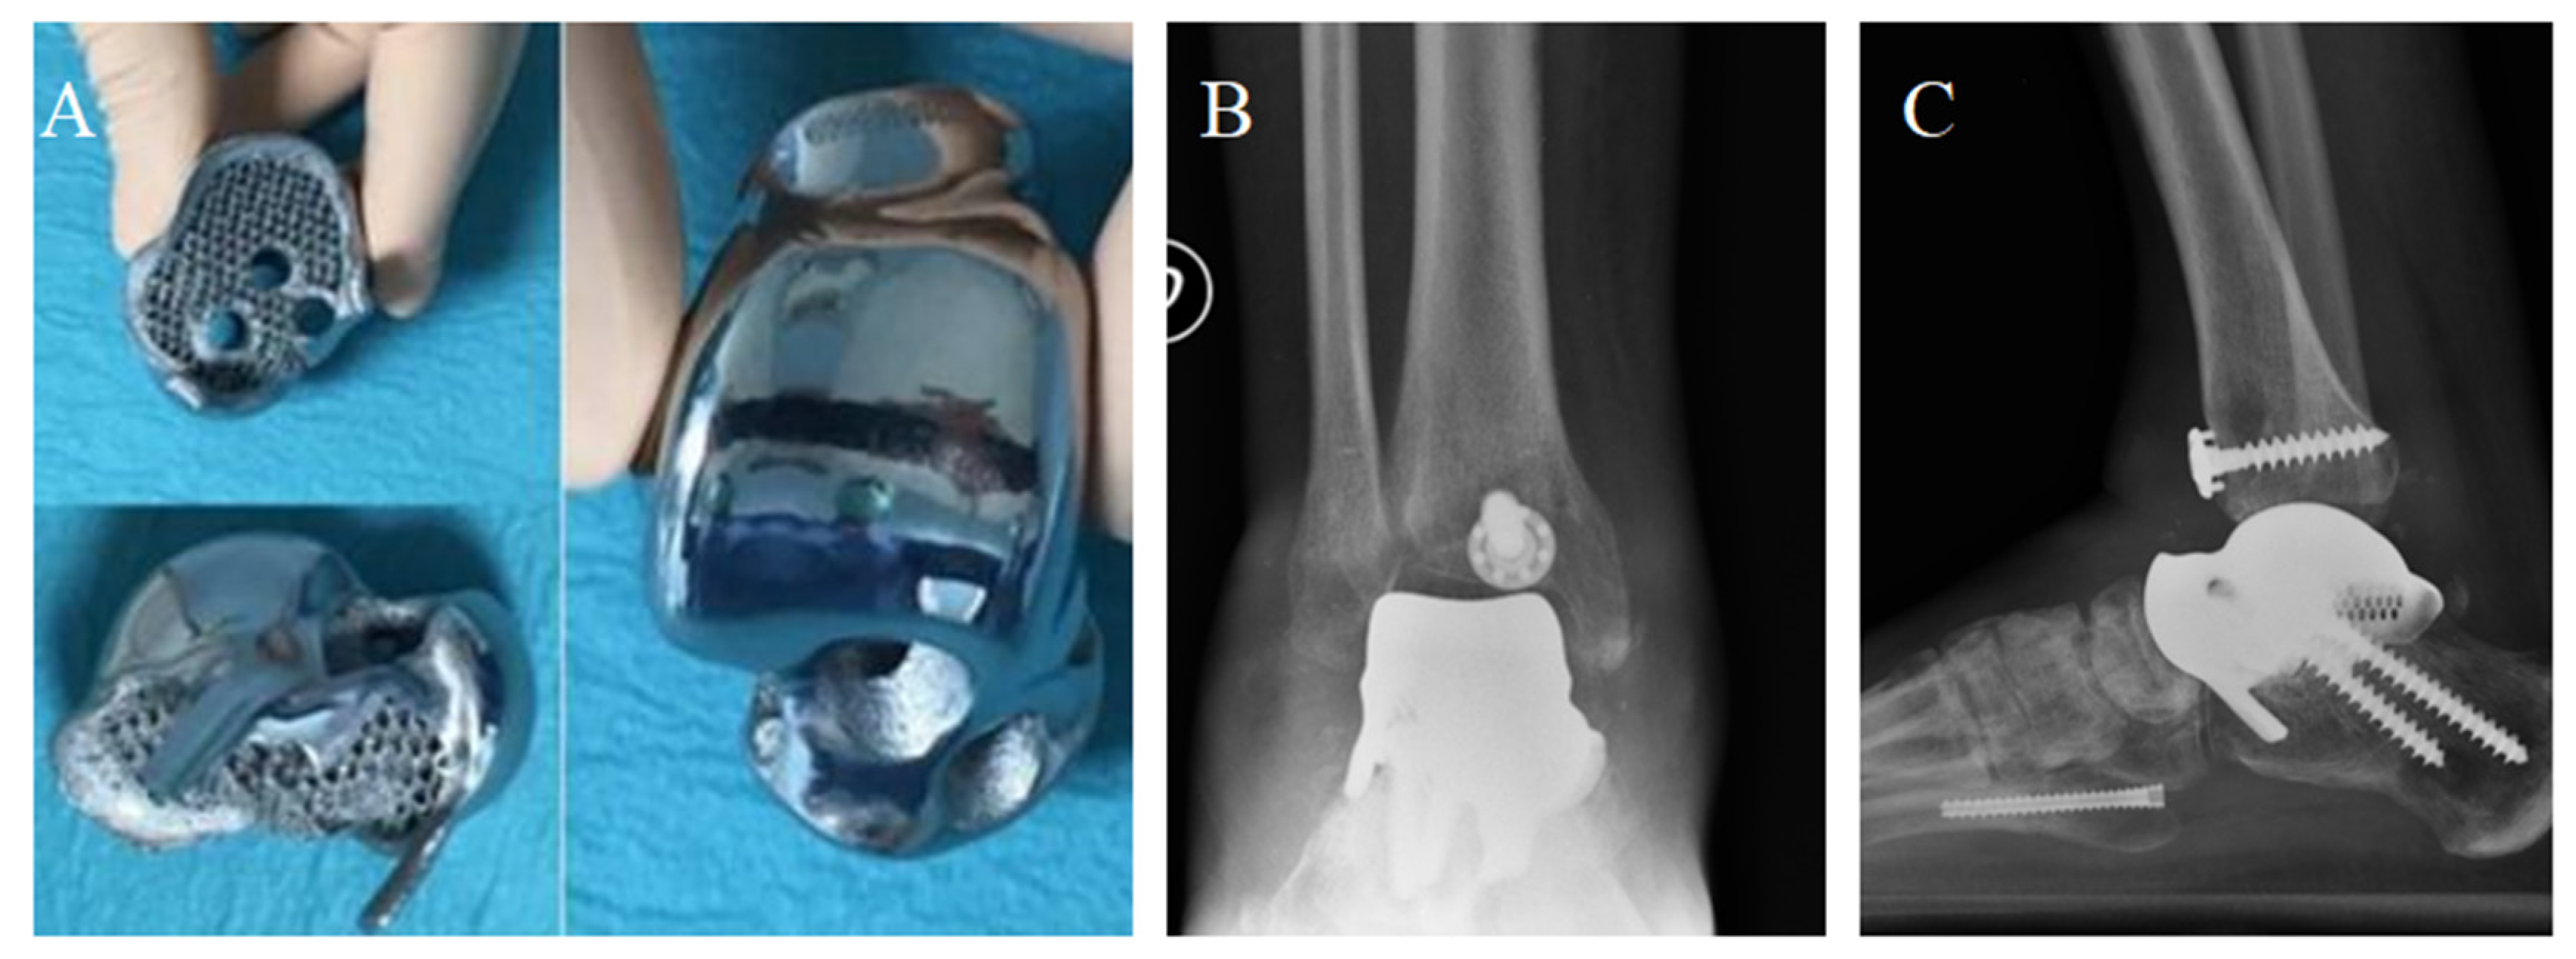

Figure 8.

The prosthesis ready to be implanted (A). X-ray of the implant from antero-posterior (B) and latero-lateral (C) projections. Articular space can be observed in figure (B).